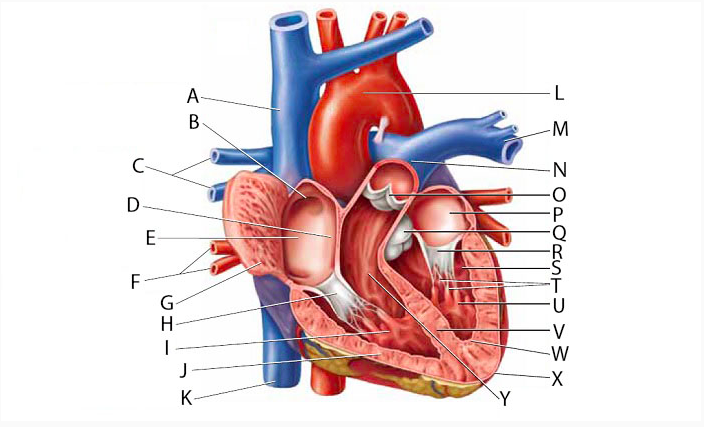

Anterior interventricular valve

Aortic Valve (=left semilunar)

Apex (of the heart)

Chordae tendineae

Coronary sinus

Endocardium

Epicardium

Left atrioventricular (=bicuspid, =mitral) valve

Left/right atrium

Left/right auricle

Left/right coronary artery

left/right ventricle

Myocardium

Papillary muscles

Pectinate muscles

Pericardial sac (=fibrous pericardium)

Pulmonary valve (=right semilunar)

Right atrioventricular (=tricuspid) valve

Superior/inferior vena cava